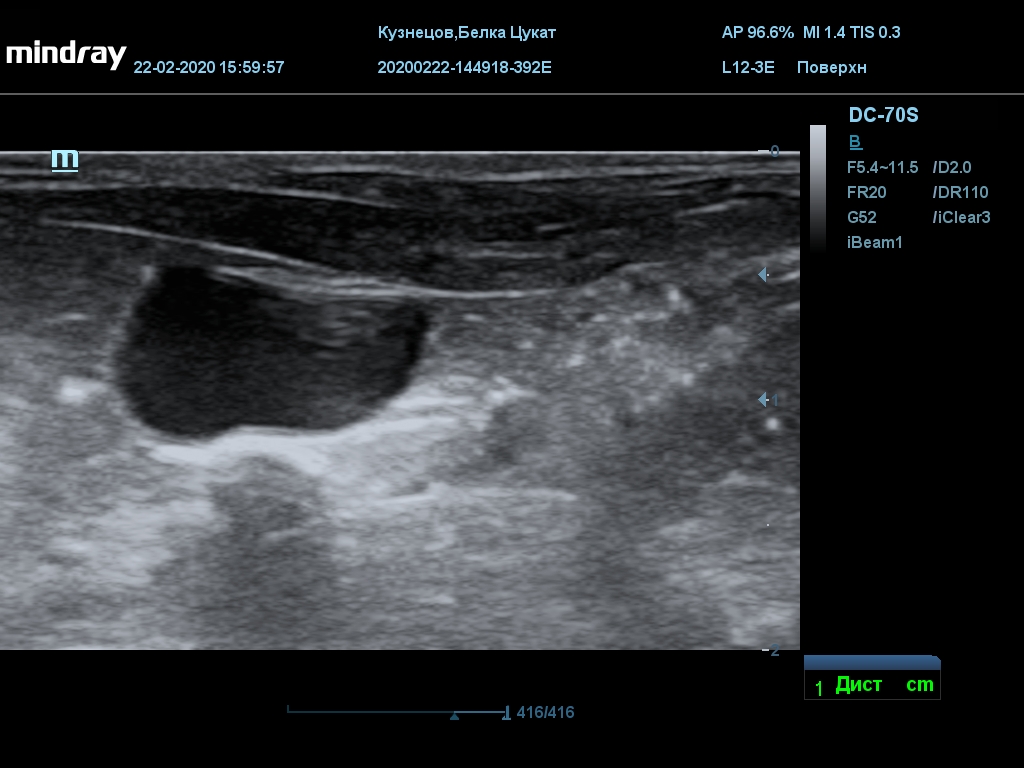

УЗИ

(почки, мочевой пузырь и, предположительно, простата)

Обращаю внимание, что делала УЗИ и писала заключение узист, которая специализируется на кошках и собаках, поэтому она сделала узи и описала, как смогла, но тонкостей грызунячьей анатомии она не знает.

Приложил только фото, есть ещё пара видео, но не знаю, как тут выложить, и надо ли.

Мочевой пузырь объём 12,1 х 7,6 х 11 мм. Стенка не утолщена, 0,5 мм, содержимое не однородное, до половины объёма гипоэхогенная мелкодисперсная взвесь. Макс. размер включений 0,8 мм. Теней нет.

Каудальнее мочевого пузыря визуализируется округлая структура размером 11,1 х 8,3 мм с ровными контурами гипоэхогенная однородная, с признаками васкуляризации.

Почка левая ровная, размер 12 х 7,6 х 8,2 мм. Контур ровный чёткий. КМД отсутствует, лоханка расширена незначительно, объёмных включений не выявлено.

Почка правая ровная, контур чёткий, размер 13,5 х 8,7 х 9,3 мм. Капсула визуализируется. КМД отсутствует, лоханка не расширена. Объёмные образования не выявлены.

Заключение: УЗпризнаки уролитиаза, объёмная структура каудальнее мочевого пузыря. Признаки расширения левой лоханки.

УЗИ

(почки, мочевой пузырь и, предположительно, простата)

Обращаю внимание, что делала УЗИ и писала заключение узист, которая специализируется на кошках и собаках, поэтому она сделала узи и описала, как смогла, но тонкостей грызунячьей анатомии она не знает.

Приложил только фото, есть ещё пара видео, но не знаю, как тут выложить, и надо ли.

Мочевой пузырь объём 12,1 х 7,6 х 11 мм. Стенка не утолщена, 0,5 мм, содержимое не однородное, до половины объёма гипоэхогенная мелкодисперсная взвесь. Макс. размер включений 0,8 мм. Теней нет.

Каудальнее мочевого пузыря визуализируется округлая структура размером 11,1 х 8,3 мм с ровными контурами гипоэхогенная однородная, с признаками васкуляризации.

Почка левая ровная, размер 12 х 7,6 х 8,2 мм. Контур ровный чёткий. КМД отсутствует, лоханка расширена незначительно, объёмных включений не выявлено.

Почка правая ровная, контур чёткий, размер 13,5 х 8,7 х 9,3 мм. Капсула визуализируется. КМД отсутствует, лоханка не расширена. Объёмные образования не выявлены.

Заключение: УЗпризнаки уролитиаза, объёмная структура каудальнее мочевого пузыря. Признаки расширения левой лоханки.